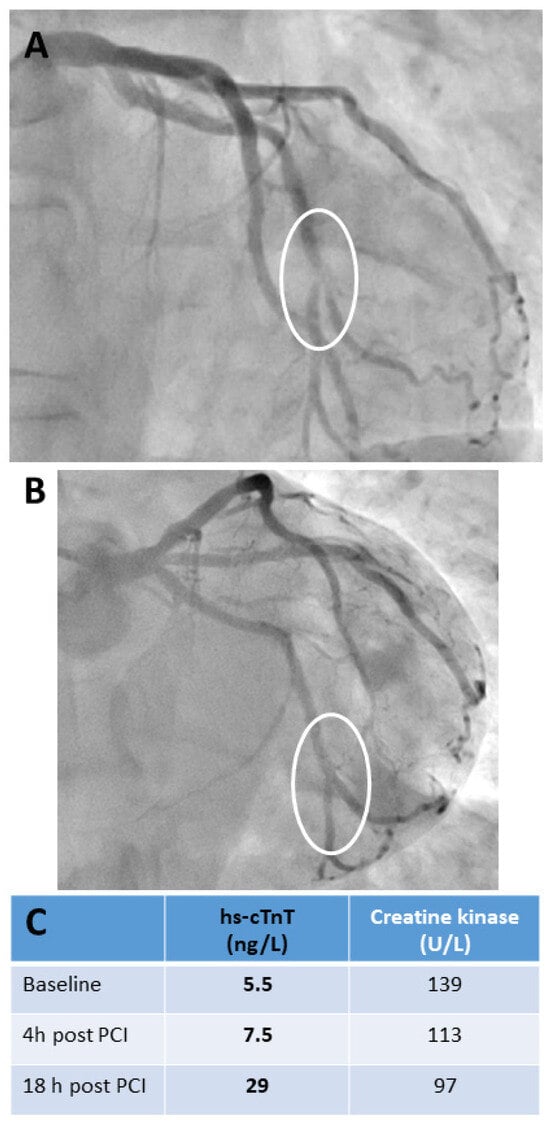

2.2.1. Clinical Implications: Challenges in Interpreting hs-cTn Concentrations Following Elective Percutaneous Coronary Interventions